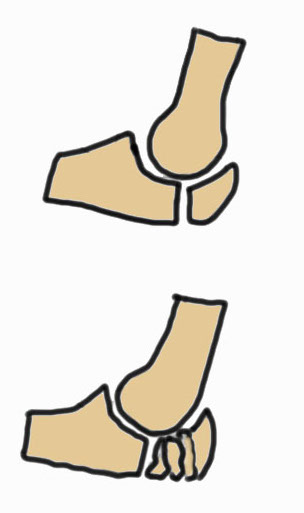

Mayo Classification

A: Non comminuted

B: Comminuted

| Type I | Type II | Type III |

| Minimally displaced | Displaced | Trans-olecranon fracture dislocation |

| 10% | 85% | 5% |